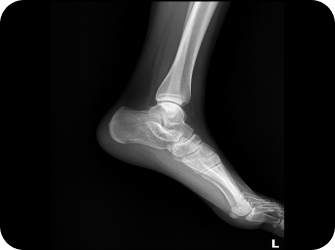

엑스레이 및 CT

발은 우리 몸에서 건물의 주춧돌과 같은 역할을 합니다. 발의 틀어짐으로 인한 통증은 단순히 발의 문제로 그치지 않고 보행 패턴을 무너뜨리며 다리와 무릎 관절, 나아가 골반과 허리의 추간판까지 연쇄적인 영향을 미칩니다. 발의 문제를 조기에 발견해 치료하는 것이 전신 건강을 위해 중요합니다.

▲ 발의 문제로 인해 생기는 요통